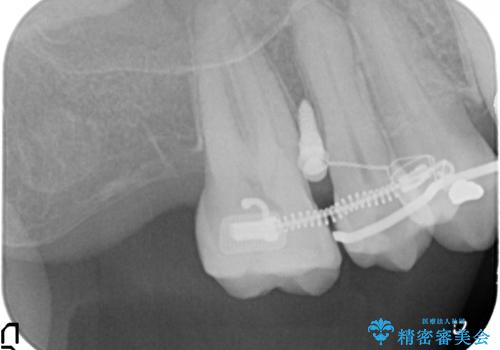

検査の結果、強い歯ぎしりによる歯の周囲の骨の吸収が認められたため歯槽骨の再生・歯周ポケットの除去・力に対抗する連結補綴・補綴前処置としての小矯正を計画します。

特定の歯に強く力がかかりまた歯周病により臨床歯根が短くなっているような場合、歯の動揺を抑えるため連結補綴が検討されます。

歯の動揺が続くとより周囲の骨を失い最終的には歯を喪失してしまう可能性が高くなってしまうためです。

今回連結補綴を行うにあたり、歯周病の問題を解決するために再生療法・歯周ポケット除去手術を、またより歯の神経を保存し力に対抗できる環境を整えるために小矯正を行い精度の高いメタルボンドクラウンを製作することができました。